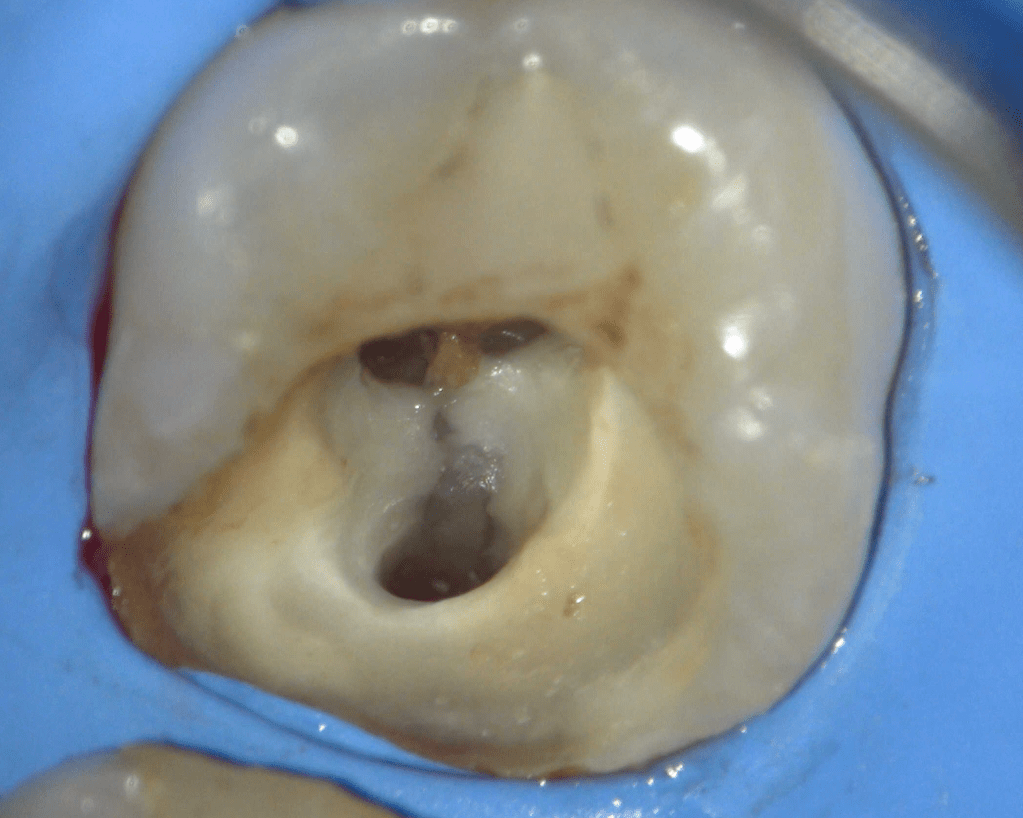

Reco preendo + 4 conductos molar superior